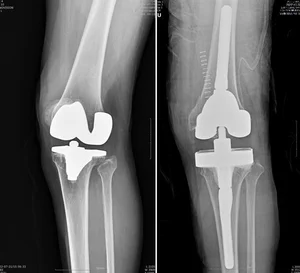

인공관절 재수술, 경험 많은 의료진이 결과 좌우

82세 A씨는 퇴행성관절염 말기 무릎 통증으로 16년 전 인공관절 치환술을 받았다. 하지만 빙판길에 넘어지면서 3년 전부터 다시금 통증이 시작됐고, 고심 끝에 병원을 찾은 그는 ‘인공관절 재치환술’을 해야 한다는 진단을 받았다.